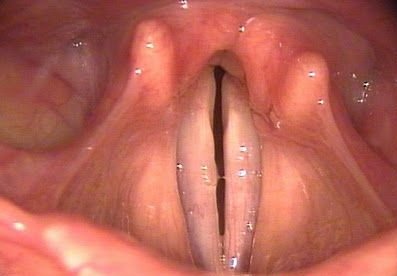

При любом обследовании пациента с парезом гортани первым этапом является микроларингоскопия, которая позволяет оценить положение голосовых связок, а также расстояние между ними и их состояние. Это исследование помогает определить состояние слизистой оболочки гортани, выявить наличие различных воспалительных процессов, включая кровоизлияния.

После изучения предъявленных жалоб и проведения внешнего осмотра шеи и ротовой полости, лечащий врач решит назначить одно из следующих обследований: ларингоскопию, которая включает изучение положения голосовых связок, выявление воспалительных процессов, оценку состояния слизистой оболочки гортани и ее целостности, томографию, рентгенографию и электромиографию для оценки состояния мышц. Для определения уровня нарушения голосовых функций также могут использоваться фонография, стробоскопия и электроглоттография.

- исследование ларингоскопией – используется для оценки положения голосовых связок, расстояния между ними, выявления воспалительных процессов или кровоизлияний